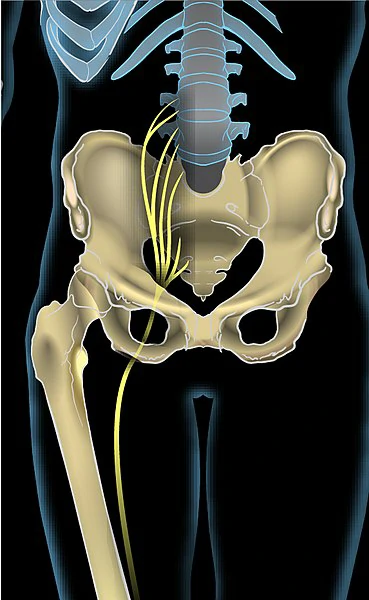

These 2 conditions share similar symptoms, however, sciatica is characterized by a compression of the sciatic nerve, which runs from the lower back, through the buttocks, and down into the leg.

It is usually a secondary condition, caused by a herniated disk, spinal stenosis, or other spinal conditions, or as a result of piriformis syndrome.

Sciatica is generally classified as either originating in the buttocks or lower back, called piriformis syndrome or sciatica respectively. Piriformis syndrome is caused by the compression of the sciatic nerve by the buttock muscles, while other causes of sciatica involve compression of the nerve in the lower back.

Unlike sciatica originating from the spine, piriformis syndrome usually starts in the buttocks and, in severe cases, may radiate down to the lower back.

Sciatica commonly affects both sides of the body with varying degrees of intensity. The symptoms of piriformis syndrome are usually limited to one side of the buttock area.